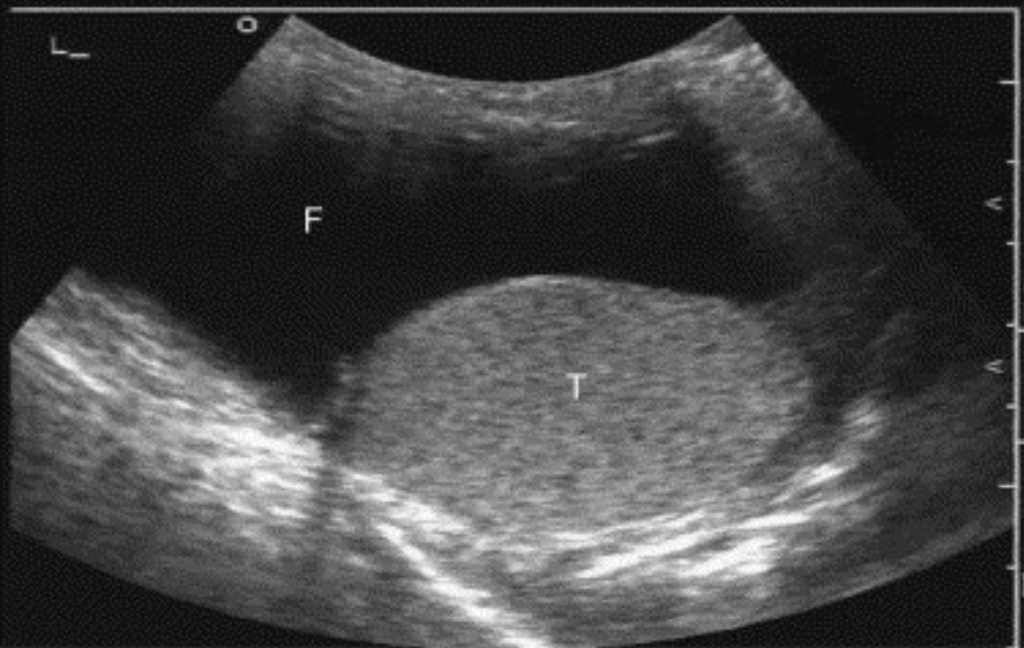

- Hydrocele

- Presentation: Painless scrotal swelling, and positive transillumination test on physical exam.

- Findings: A hydrocele appears as an anechoic fluid collection between the parietal and visceral layers of the tunica vaginalis, and can contain low-level echogenic foci if proteinaceous or infected.

- Note: Hydroceles are either primary, due to incomplete closure of the processus vaginalis, or secondary, caused by infection, trauma, or malignancy.

- Management: Typically self-resolving, so treatment is rarely necessary unless secondary to another pathology.

Hydrocele – anechoic fluid (F) surrounding testis (T).